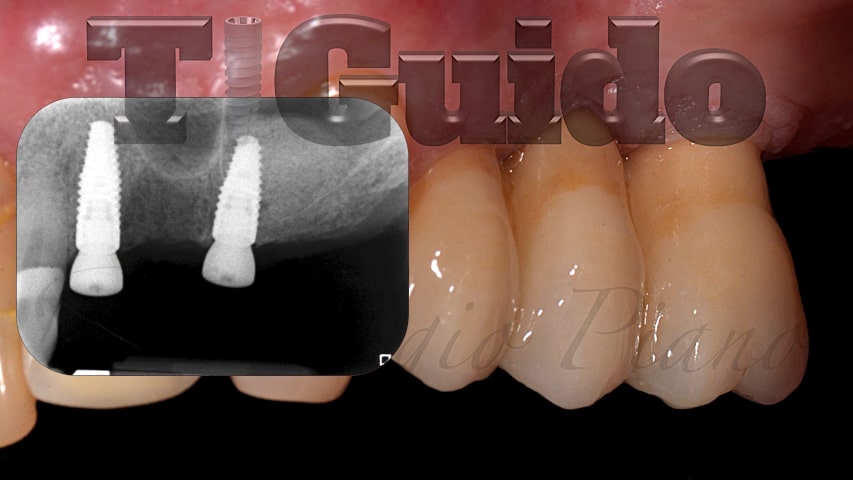

Alcuni nostri casi